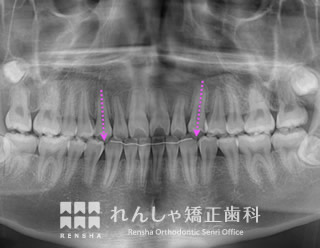

補綴前矯正(26歳 治療期間:2年2か月)

右下の永久歯が先天的に欠損していたため、下前歯は右側に偏っていました。

左側の噛み合わせに大きな問題はなかったことから、右上前歯のがたつきを改善し、右下には1歯分のスペースを確保してインプラント治療を受けていただきました。

| 主訴 | 上前歯のがたつきと右下の永久歯が1本足りない |

|---|---|

| 診断名 | Angle Class I 叢生 |

| 初診時年齢 | 26歳10か月 |

| 装置名 | マルチブラケット装置 |

| 抜歯非抜歯 | 非抜歯 |

| 治療期間 | 2年2か月 |

| 費用の目安 | 約90万円+消費税(検査料金、都度の処置費用等も合わせた総額) |

| リスク副作用 | 歯の移動に伴う軽微な歯根吸収、歯槽骨吸収、歯肉退縮(いずれも本症例ではほぼ無し)、矯正器具装着中のカリエスリスク増大(本症例では臼歯にカリエスが発生し、その後う蝕処置) |